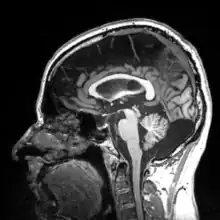

Recent studies by Emiliano Bruner, Manuel Martin-Loechesb, Miguel Burgaletac, and Roberto Colomc have investigated the connection between midsagittal brain shape and mental speed. This study incorporated human subjects' cognitive testing in relationship to extinct humans. They used 2D from 102 MRI-scanned young adult human for comparison. Such correlations are small, suggesting that the influence of midsagittal brain geometry on individual cognitive performance is negligible but still provides useful information of evolutionary traits of the brain. Areas associated with the parietal cortex appear to be involved in relationships between brain geometry and mental speed.[18]